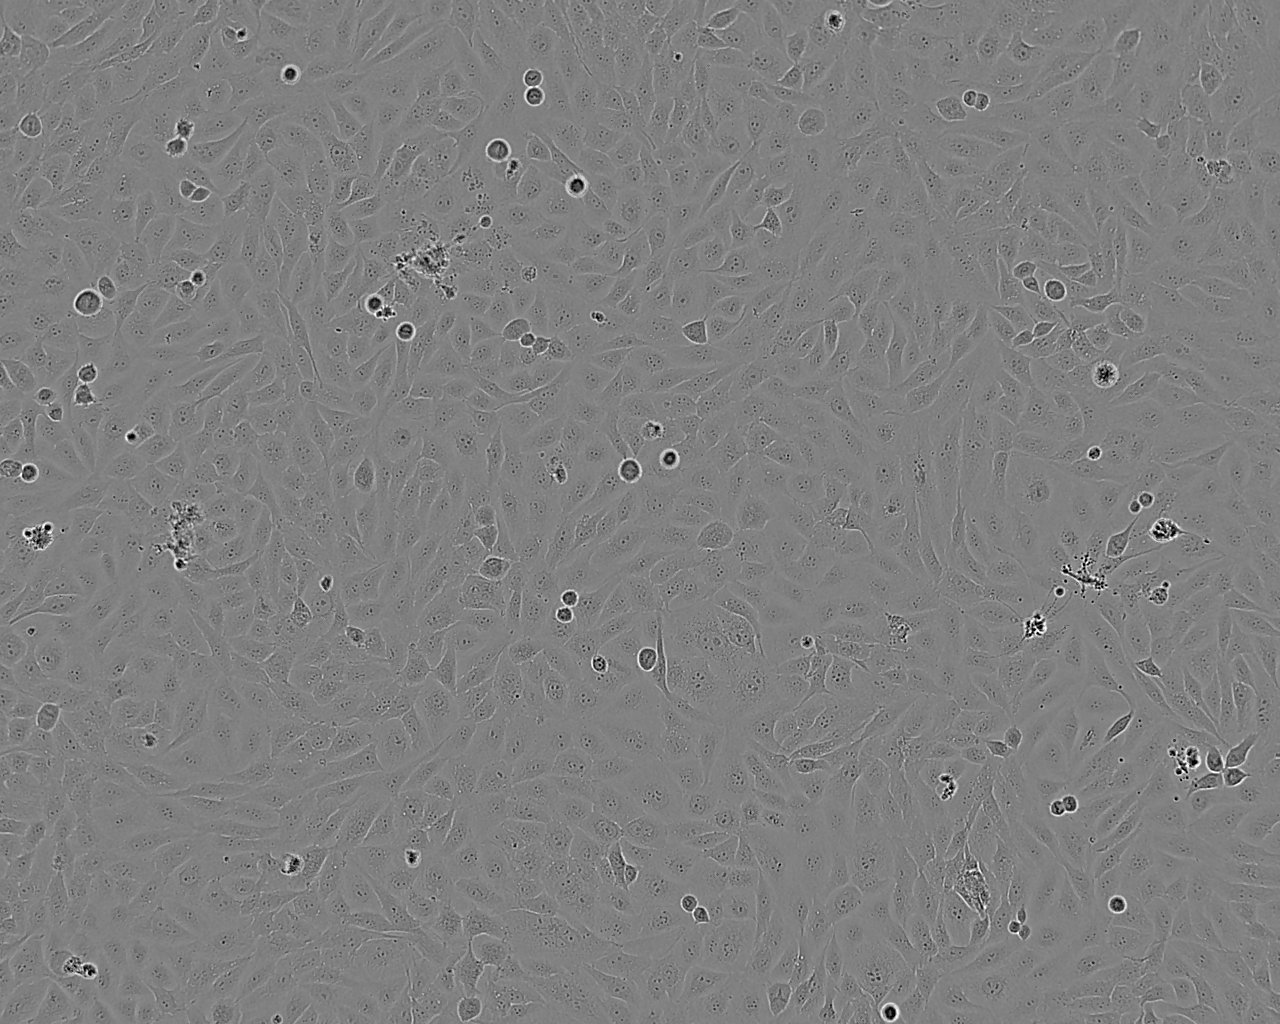

细胞背景资料:MSTO-211H细胞株是1985年从一位肺二相间皮瘤患者的胸水中建株的。这个病人接受过多种药物联合前期化疗。MSTO-211H细胞具有高亲和力的EGF结合位点,并表达神经元特异性烯醇酶(NSE)及人绒毛膜促性腺激素(HCG)的α与β亚基。未检测到左旋多巴胺脱羧酶(DDC),邦巴辛与神经tensin。细胞过表达c-myc原癌基因,并没有观察到基因重排或扩增。V-src,v-abl,v-erbB,c-raf1,Ha-ras,Ki-ras,和N-ras的表达呈阳性。未检测到N-m

细胞形态:上皮细胞样

细胞生长:贴壁

细胞生长特性:贴壁生长